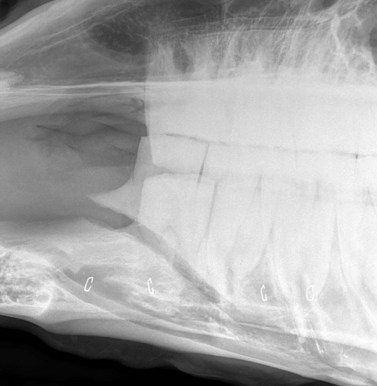

Fractures of the caudal mandible

Fractures involving the horizontal ramus in the region of the molar teeth are typically unilateral with minimal displacement or comminution (Fig. 9.28). They typically arise from external trauma, such as a kick injury or fall, but iatrogenic fractures arising from dental repulsion procedures are also encountered. Aside from painful mastication, clinical signs may be non-specific. Thickening of the horizontal ramus may be noted, both externally and upon intra-oral examination; this may be subtle and tends to be generalized rather than the focal thickening seen with dental apical infection. Close examination of the oral cavity may also reveal some mucosal bruising in the region of the fracture line and on occasion there is concurrent (usually transverse) fracture of an adjacent cheek tooth.

image

Fig. 9.28 Fracture of horizontal ramus involving a tooth.